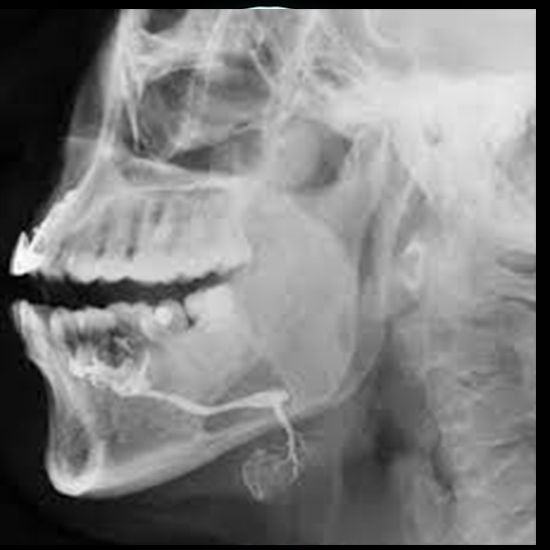

A Sialogram Imaging is a method for seeing the salivary gland located in the mouth. Salivary glands in the mouth produce saliva, which aids in chewing, swallowing, and digestion. This test detects any obstruction, constriction, or dilation in the gland. It is advised for oral pain, swelling, dryness, or unpleasant taste.